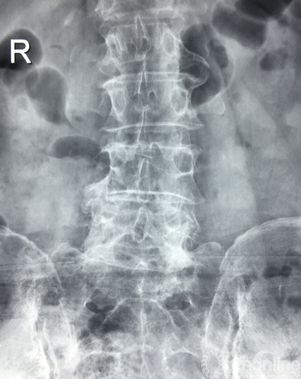

正位X片